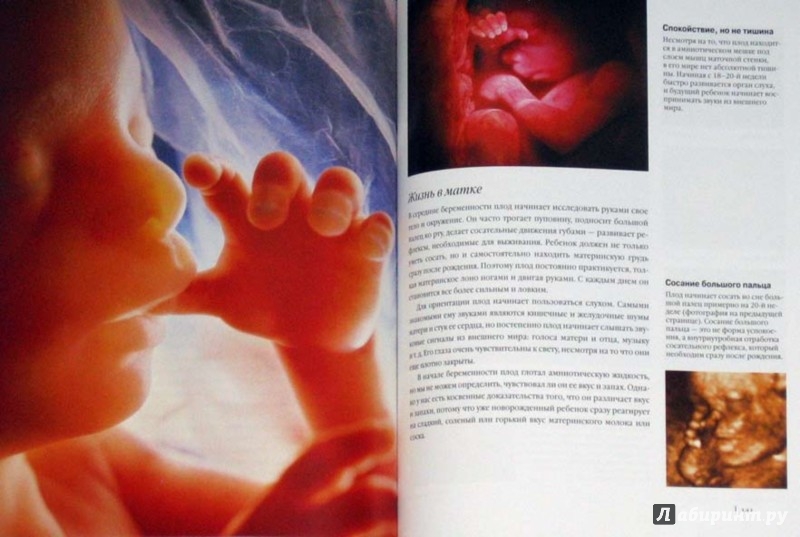

Зарождение жизни: Фотографии Леннарта Нильсона

Раздел: Идеи и советы